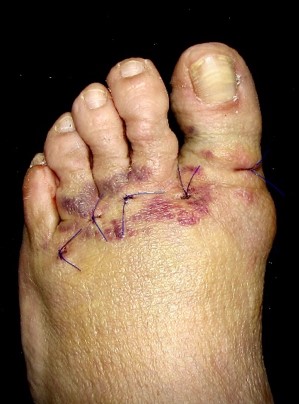

Figura 2a

Figura 2b

Figura 2c

Figura 2d

Figura 2e

Figura 2f

Figura 2. Técnica quirúrgica a) osteotomía DMMO percutánea, b) imagen fluoroscópica de las osteotomías, c) sutura, d) vendaje postquirúrgico con cinchas invertidas para mantener la alineación de los metatarsianos, d, e) vendaje definitivo postquirúrgico, f) paciente al salir de quirófano con apoyo completo y zapato de suela plana y recta